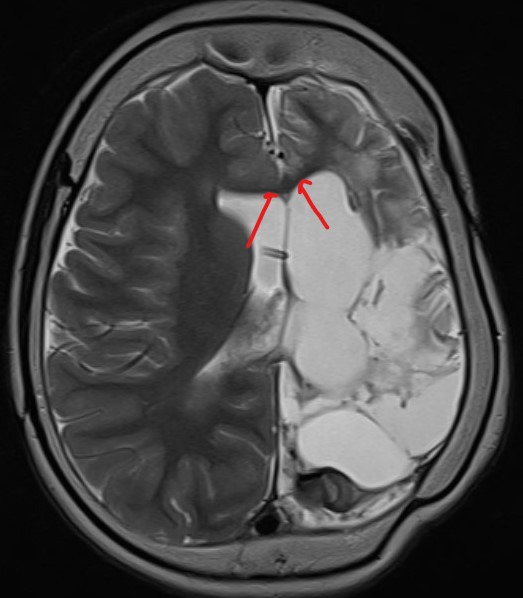

While there is an asymmetry of beta frequencies on the common average montage, especially over the central-parietal regions, the asymmetry is easily missed. The bipolar montage demonstrates suppression of normal rhythms over the left hemisphere; the suppression over the left hemisphere cannot be appreciated on the referential montage. The EEG has been performed on a patient who has previously had a left hemispherectomy.

The following images accompany comments at the foot of this post.